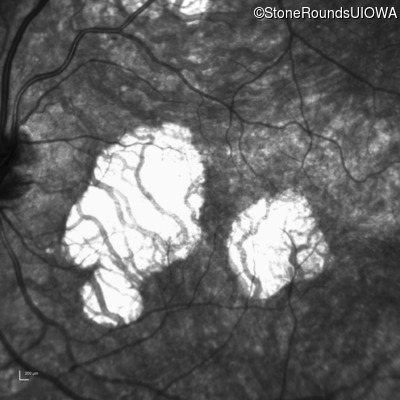

Infrared Fundus Photograph - Right - 20/20 sc

Exemplar